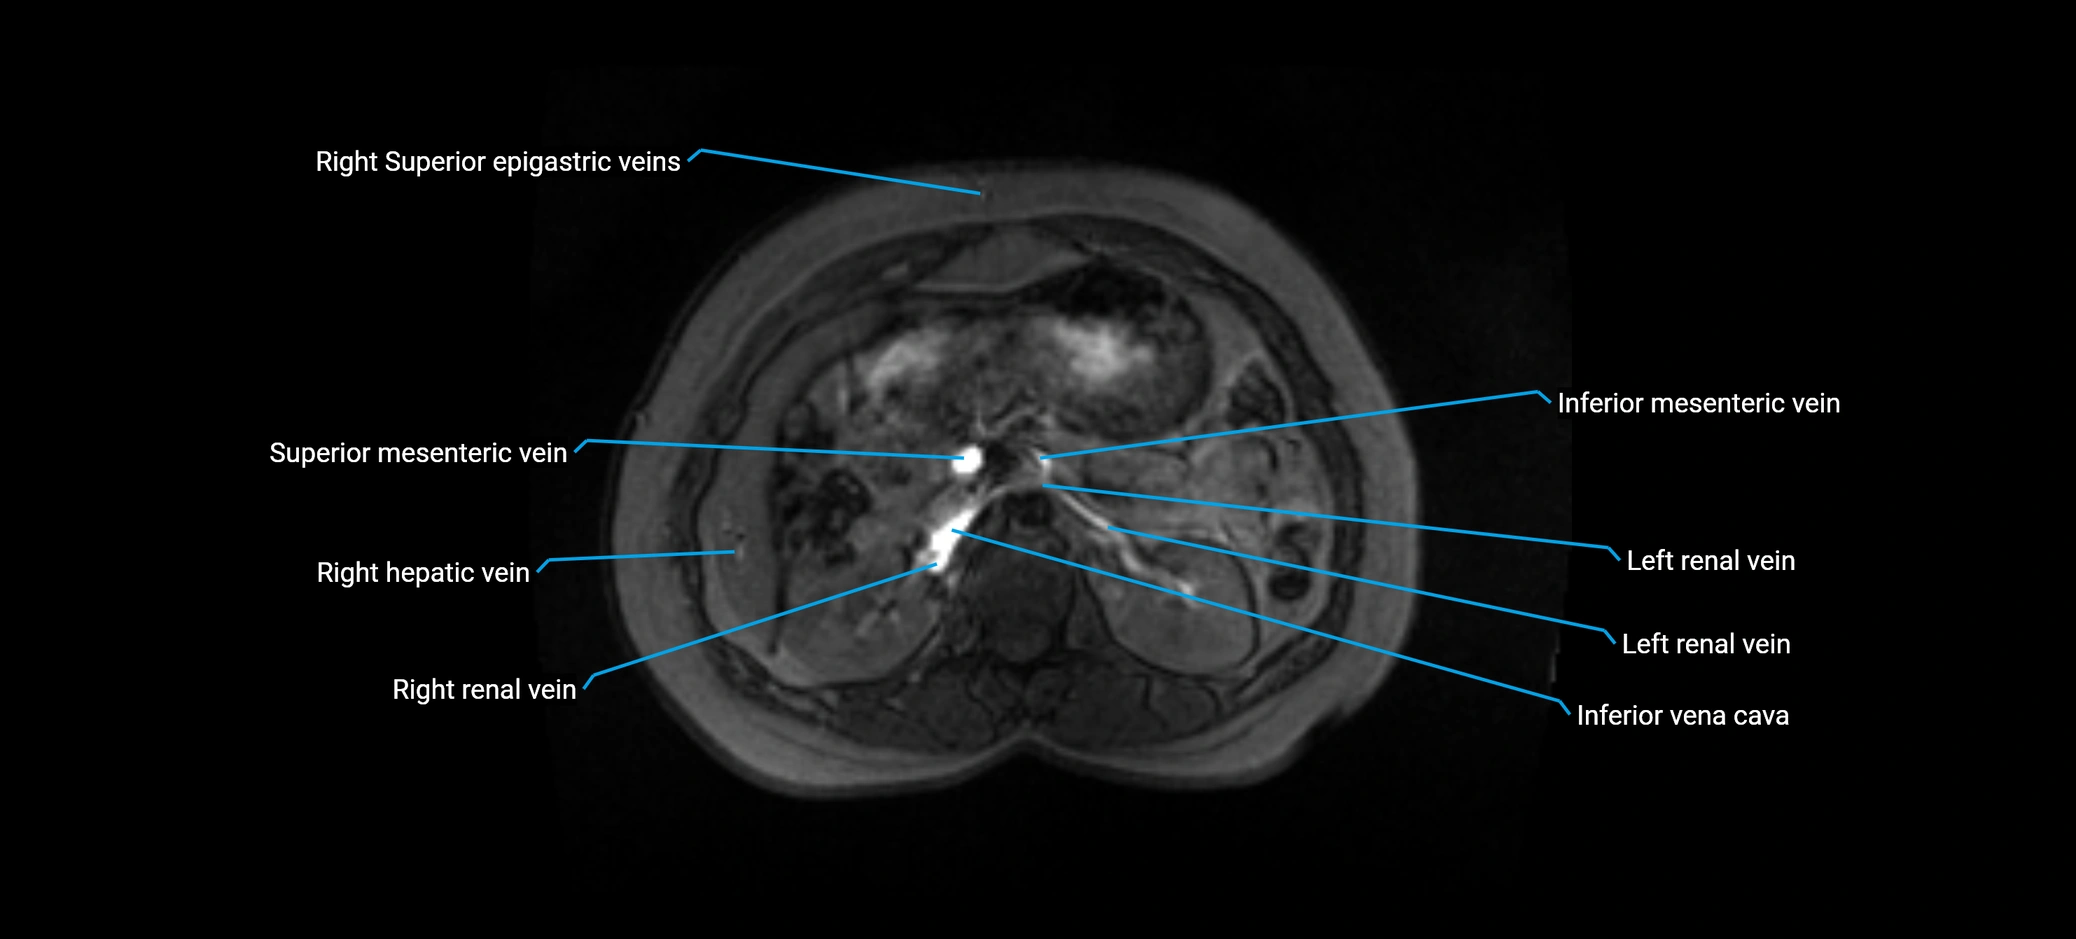

MRI image

image